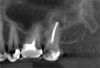

Because of its high resolution and ability to discern between bone and soft tissue, CBCT is the gold standard radiographic exam for the diagnosis of MSEO.2,12,18,20 CBCT imaging provides several advantages over traditional 2-dimensional dental radiographs. On periapical radiographs, anatomic noise imparted by the overlapping structures of the maxillary sinus and zygomatic process can conceal the inflammatory changes associated with apical periodontitis.9,29 Furthermore, 2-D radiographs do not adequately describe the anatomical relationship between the teeth and the sinus floor (Figure 2).3,9

For patients suffering from MSEO, radiographs will reveal a periapical radiolucency with adjacent opacification in the maxillary sinus.12 Additional radiographic findings associated with MSEO include periapical mucositis and periapical osteoperiostitis (PAO). Periapical mucositis refers to mucosal thickening or dome-shaped soft-tissue expansion on the floor of the sinus directly adjacent to the infected root apex.PAO refers to the reactive osteogenesis caused by a local periosteal reaction that expands the sinus periosteum and displaces it upward into the sinus. It appears as a radiopaque "halo" surrounding the root apex (Figure 2 through Figure 4). PAO may be symptomatic and/or accompanied by adjacent mucosal edema and elevated sinus fluid levels.9 If left untreated, PAO can progress and result in a direct communication between the root apex and maxillary sinus.6,13 Unless bilateral odontogenic pathosis is found, the sinus opacifications will usually be unilateral and centered around the odontogenic source. Complete unilateral sinus opacifications may be missed on the CBCT images typically used in endodontics due to their limited or focused field of view (Figure 5). In cases involving complete unilateral sinus opacification, referral to an ENT or oral surgeon is essential to rule out invasive fungal infection or malignancy.2,17,24

(2.) Radiograph of PAO showing necrotic tooth with sinus pathosis obscured by the zygoma.

Figure 2